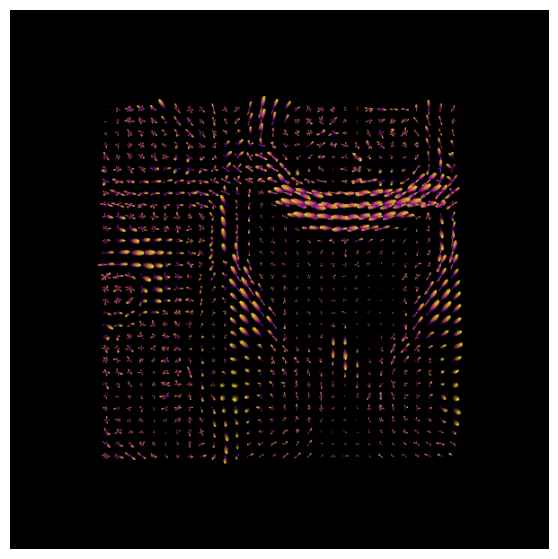

We will now use the basis functions generated above to create Fiber Orientation Densities, or FODs. These are estimates of the amount of diffusion in each of three orthogonal directions. As described in the introductory chapter, these are analogous to the tensors that are used in traditional diffusion studies. However, MRtrix allows for the estimation of multiple crossing fibers within a single voxel, and can resolve the diffusion signal into multiple directions.

To do this, we will use the command dwi2fod

to apply the basis functions to the diffusion data. The “-mask” option specifies which voxels we will use; this is simply to restrict our analysis to brain voxels and reduce the computing time. The “.mif” files specified after each basis function will output an FOD image for that tissue type:

In order to view these FODs, we will combine them into a single image. The command mrconvert

will extract the first image from the wmfod.mif file, which is the image with a b-value of 0. The output of this command is then used as the input into an mrcat

command which combines the FOD images from all three tissue types into a single image that we will call “vf.mif”:

The white matter FODs can then be overlaid on this image, so that we can observe whether the white matter FODs do indeed fall within the white matter, and also whether they are along the orientations that we would expect. The command for mrview is:

mrview vf.mif -odf.load_sh wmfod.mif